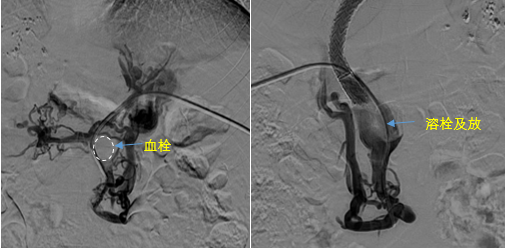

在西安國際醫(yī)學中心醫(yī)院,韓國宏教授對李女士進行了細致的問診及檢查,在CT圖像上仔細的分析,針對患者特殊的病情制定了詳細的治療方案。第一次進入手術室,在DSA的監(jiān)測下,造影過程中門靜脈血栓的輪廓逐漸顯現出來,見多識廣的醫(yī)生們也大吃一驚,發(fā)現遠端脾靜脈及腸系膜上靜脈也存在大量血栓?;颊叩氖彻芪傅嘴o脈曲張非常嚴重,疏通堵塞的門靜脈已是刻不容緩。

見此情形,韓國宏教授憑借豐富的臨床經驗很快調整了策略,在超聲診療中心的協(xié)助下進行門靜脈右支穿刺,并進行造影,看到目標血管后,韓國宏教授用“明修棧道,暗渡陳倉”的方法,讓來自脾臟和胃腸的血流終于暢通的回流到了肝靜脈。通過血流的沖刷以及抗凝溶栓藥物的作用,幾日后復查造影發(fā)現門靜脈血栓已逐漸變小,不會對回流到肝臟的血流產生大的阻礙作用,門靜脈的壓力顯著減小,患者再次出血的幾率也隨之降低。幾經周折,這顆“定時炸彈”終于被拆除,李女士和她的家人多年來心里的石頭也終于落地。